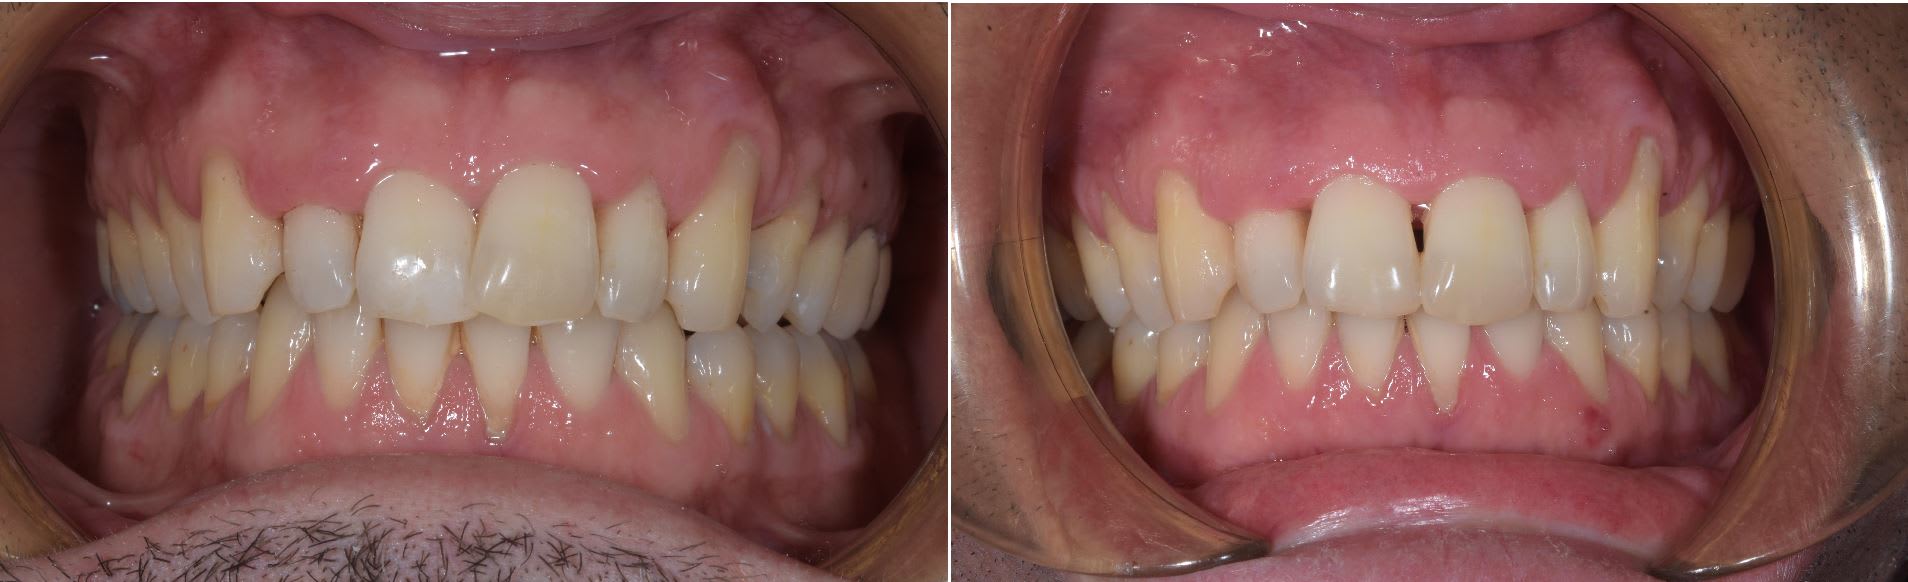

Et un cas commencé par un généraliste dans mon hopital.

Celuis présenté en début de fil avec le patient edge to edeg.

Ici je n'ai strictement rien fait même pas controler la position des bracket sur le modéle en plâtre ou aider pour plier le fil.

Pas de set up 3D imprimé pour ce cas.

Juste indiquer de commencer par aligner le haut pour creer un overjet.

Un mois avec les bague et bonne proclination alignement .

La photo initial n'est pas la mienne je précise.

Comme d'hab la patiente ( une assistante ) ne sens rien et n'a aucun problème pour parler.